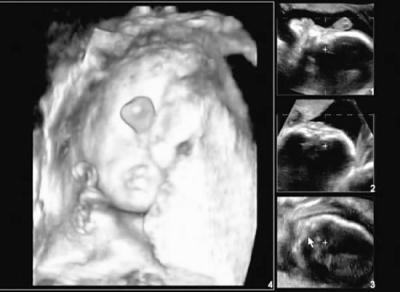

昨日,38岁的孕妇卢欣(化名)满怀喜悦的心情来到医院。她打算在怀孕26周时,做个三维彩超,给即将出生的宝宝留下第一张人生“近照”。然而当超声科的医生将探头放在了她肚子上时,不禁吃了一惊:“胎儿仅有一只眼睛,长在鼻子下方,鼻子像一团小肉,四肢都是六个指(趾)头,内脏更是畸形多多!”

据悉,像卢欣腹中胎儿的这种畸形,平均6万至10万新生儿中会有1例,相对来说还是罕见的。

超声科的潘农主任分析说,尽管致畸原因至今不明,但可能跟染色体异常有一定关系。胎儿往往在发育中先发生某一种畸形,之后再导致相关组织、器官的一系列畸形。潘医生婉惜地说:“孕妇要是早一点就来做孕期检查就好了,她本身就属于高龄孕妇,在怀孕、生产过程中风险性要比一般孕妇要高得多,胎儿畸形和遗传性疾病的几率也相对较大,如果说能够在怀孕11~14周,即怀孕3个月左右做一个胎儿颈部透明带的测试,便可发现胎儿发育的异常。”

颈部透明带的测试怎么回事?会伤害到胎儿吗?专家解析,是一种通过超声波来测量胎儿皮肤和软组织之间的最大空隙厚度,绝大多数正常胎儿都可看到此透明带,但染色体异常的胎儿,其颈部透明带会明显增厚。